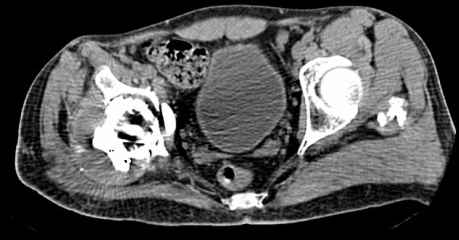

Мужчина, 45 лет. 6 мес. назад перенес тотальное эндопротезирование правого тазобедренного сустава по поводу ложного сустава шейки бедра.

Характер реконструкции вертлужной впадины не известен. Через 3 мес. после операции отметил щелчки и хруст при движениях в области эндопротеза. В анамнезе туберкулез легких. Сейчас, по заключению фтизиатра, в легких активного процесса нет. Местного воспаления нет.Предполагается нестабильность чашки в связи с бактериальным воспалением. Планируется удаление чашки и цемента, пластика дна измельченными аутотрансплантами и гидроксилапатитной керамикой, затем кольцо Мюллер, цементная чашка.

Смущает и ножка - зона просветления вокруг мантии. Предложения по тактике?

прямо скажем, очень загадочная конструкция с проволокой и винтами. :) На основании чего Вы подозреваете септическую нестабильность? Каковы результаты анализов? Согласен с доктором - нужно сделать пункцию. Есть ли снимки до и сразу после операции? Знаете ли Вы диаметр головки,какой будет внутренний диаметр Вашей чашки? Известно ли, чей протез? Может есть смысл найти автора работы и узнать о подробностях установки протеза?